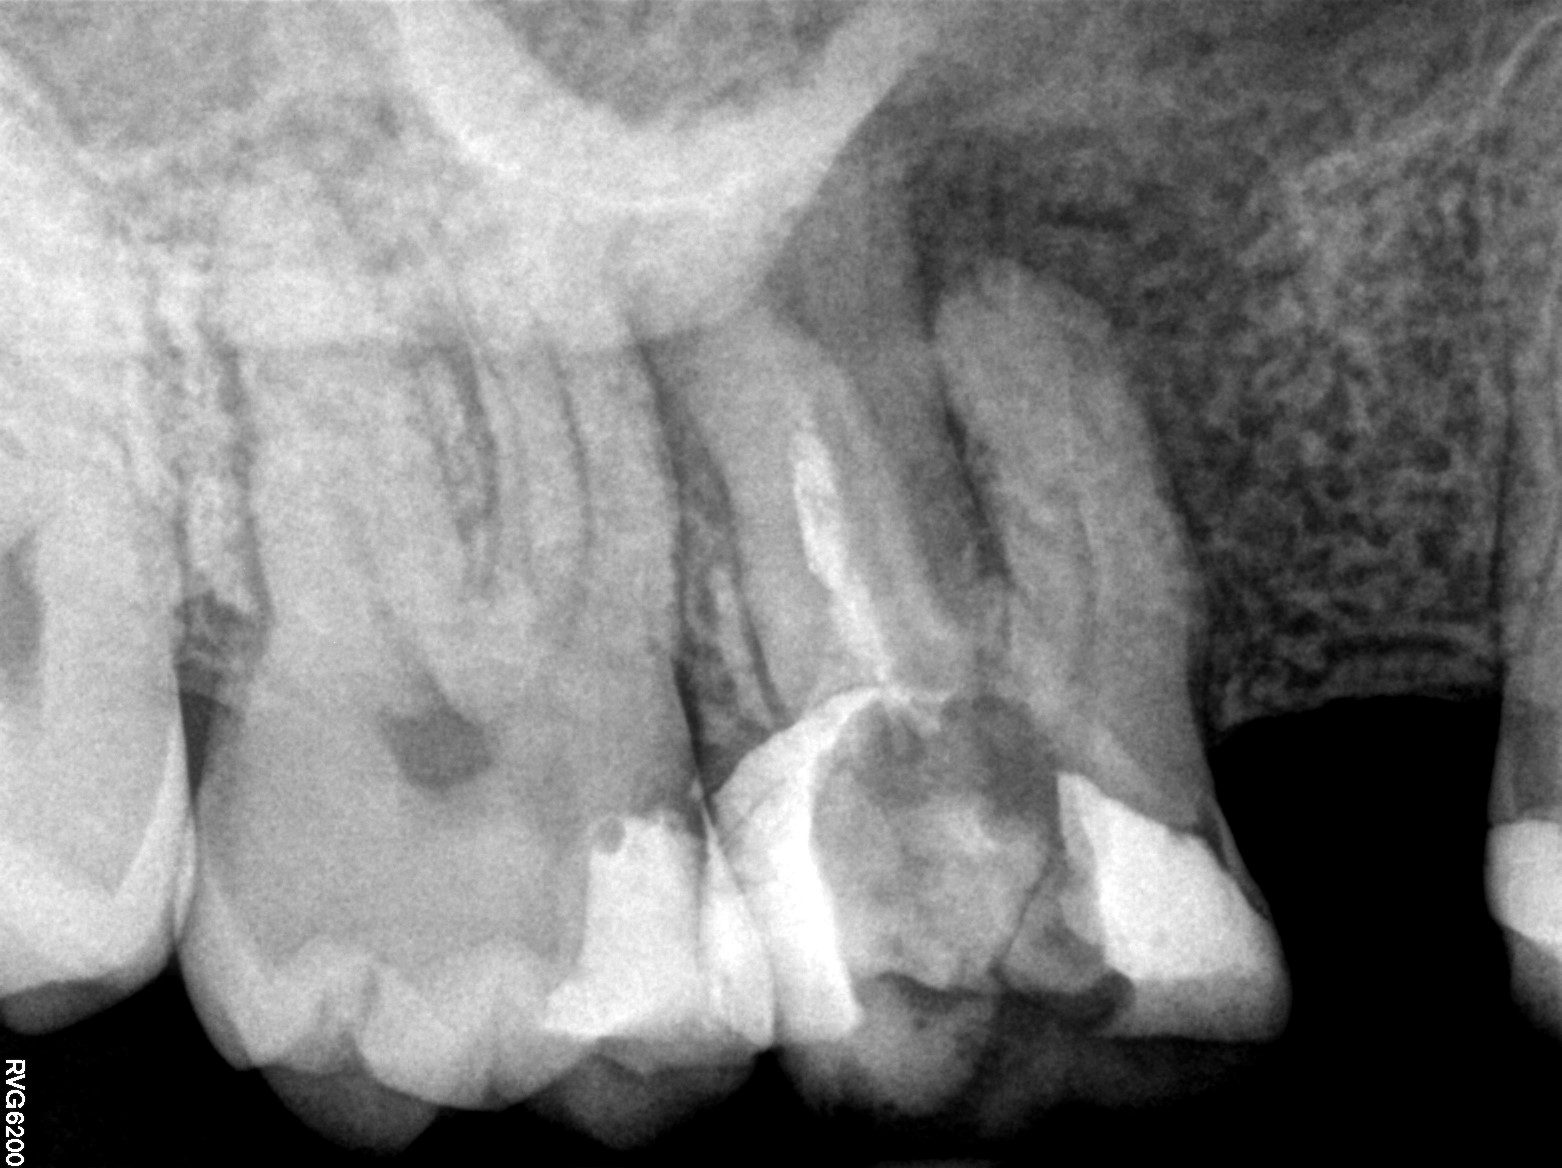

Do wizyty w gabinecie skłoniło pacjenta pobolewanie zęba, trwające od kilku tygodni, stale przybierające na sile. Pacjent nie gorączkował. Wykonano zdjęcie punktowe (ryc. 1), na którym stwierdzono obecność zmiany okołowierzchołkowej i niewłaściwie przeprowadzone, kilka lat wcześniej, leczenie kanałowe. Rozpoznanie wstępne wskazywało na przewlekłe ziarninowe zapalenie tkanek okołowierzchołkowych.

Ryc. 1. Zdjęcie zęba 16 przed leczeniem wykonane w systemie radiografii cyfrowej.